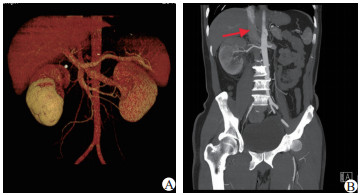

急诊医师予以解痉止痛后症状稍缓解。请泌尿外科会诊后考虑:1.急性肾绞痛;2.右侧输尿管结石?故转入泌尿外科治疗,行泌尿系统CTU示:1.右肾体积增大,右肾周、输尿管走行区周围脂肪间隙内多发渗出,右肾强化程度明显减低;2.CTU期右侧肾盂、输尿管未显影。患者目前检查无结石证据,但腰痛及血尿症状明显,暂不能排外肿瘤,故继续完善连续3 d尿脱落细胞学(后续结果:标本中见少量尿路上皮细胞,炎症细胞,未查见恶性肿瘤细胞)。继续行CTA(图 1)示:1.右肾静脉至下腔静脉血栓形成,右肾功能减低。2.右侧肾盂及输尿管壁增厚同前CT所示,周围渗出较前吸收。请肾内科会诊, 进一步查24 h尿蛋白定量为4.75 g/d(正常值0~80 mg/d),综合患者血白蛋白低,为24.7 g/L,诊断:肾病综合征。请血管外科会诊,建议抗凝治疗:伊诺肝素钠4 000 U/12 h皮下注射。抗凝一周后患者肌酐已降至正常。患者病情平稳后,转入肾内科治疗,予以正规疗程激素治疗:甲泼尼龙48 mg/d口服,补充人血白蛋白,并口服降脂药物、抗凝药物和胃黏膜保护剂。2个月后复查CT示:右肾体积较前明显缩小,右肾静脉显影良好,肾周以及输尿管周围渗出明显吸收,但左肾静脉内可见条状充盈缺损,血栓形成可能,下腔静脉显影良好,未见充盈缺损。

| 图 1 患者CTA结果(A:3D血管显像;B:箭头示右肾静脉血栓) |

肾静脉血栓(RVT)是肾静脉主干和(或)分支的血栓形成,可发生于单侧或双侧,其部分或全部阻塞而随之出现的一系列病理改变和临床表现[3]。一般临床上急性起病者多见, 多数表现为腰痛(可为绞痛)或腹痛、发热和肉眼血尿(可为浓茶水样或条状血块), 检查尿蛋白增加, 肾功能下降。CT(或超声)可发现患肾体积增大[4-5],肾周渗出明显。若双侧肾静脉主干血栓可出现肌酐骤升、电解质紊乱、少尿甚至无尿等急性肾功能衰竭的表现, 预后不好。以肾绞痛首发的RVT极为少见,临床症状和辅助检查与泌尿系统结石极度相似,故极易误诊。一般而言,对于肾绞痛患者,需要通过详细的问诊查体排除急腹症(如胆囊炎、肠梗阻)及椎间盘疾病,年轻女性还需排外妇科疾病,高度怀疑为泌尿系统疾病后再针对性地选择辅助检查。本例患者表现为蛋白尿、低蛋白血症、条状血尿,CT示患肾体积增大及明显的肾脏低灌注征象,提示并非常规性的梗阻性疾病,故最终行CTA才明确诊断。